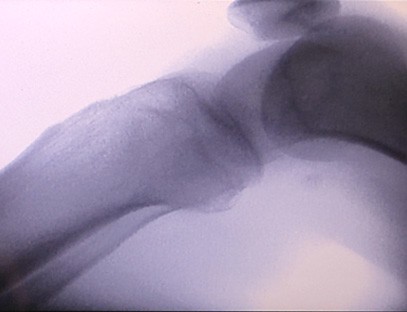

Una màquina de raigs X portàtilés un instrument portàtil de baixa dosi de radiació i molt segur que pot obtenir imatges d'alta qualitat alhora que redueix l'exposició a la radiació. Compensa les deficiències dels grans equips hospitalaris i es pot moure i transportar en qualsevol moment. Especialment indicat per a unitats i particulars amb pressupost insuficient i requeriments baixos d'imatges. La nostra màquina de raigs X de nova generació està equipada amb una pantalla gran d'alta definició de 10 polzades, que té un rang d'angle de visió més gran i pot veure completament a través de tota la palma, incloses fractures, luxacions, artritis i tumors ossis. Es pot connectar a una impressora de pel·lícules per imprimir pel·lícules ortopèdiques i també es pot utilitzar per a la producció i proves industrials. No cal una cambra fosca, perspectiva directa, observació en temps real. Aquesta màquina té un sistema d'imatge d'alta resolució que pot capturar imatges de qualsevol estructura òssia de manera molt clara. Proporcionar els millors equips i solucions de proves de raigs X per a fabricants de productes mèdics, mascotes, industrials, electrònics, departaments d'inspecció i manteniment i laboratoris d'investigació.

Especialització:Dissenyat per a les necessitats de les clíniques ortopèdiques, especialment indicat perImatge de raigs Xd'extremitats com mans, canells, colzes, espatlles, genolls, turmells, etc.

Imatge clara:La tecnologia d'imatge digital avançada s'utilitza per proporcionar imatges de raigs X d'alta qualitat, ajudant els metges a diagnosticar la malaltia amb precisió.